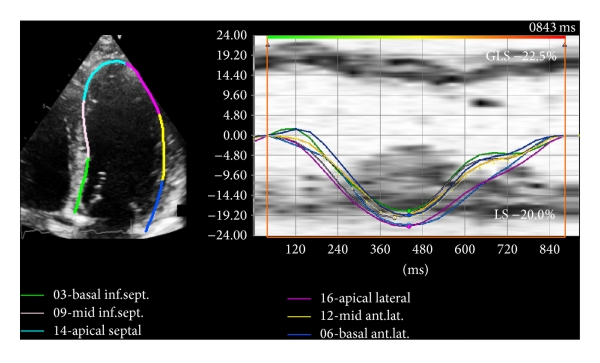

Myocardial peak systolic longitudinal strain was measured offline for both the LV and RV based on the ASE recommendations [21] using commercially available software (Vector Velocity Imaging (VVI) 3.0, Siemens Medical Solutions, Mountain View, CA) using the speckle tracking technique. Briefly, apical 4-, 3-, and 2-chamber images of the LV and an apical 4-chamber view of the RV in DICOM format were obtained for each patient and loaded into the VVI software. Endocardial contours were drawn along the LV and RV border separately for measurement of respective longitudinal strain values (Figures 1 and 2). The contours were adjusted as needed to ensure adequate visual tracking of the endocardium. Any segments that were not tracked adequately after 5 attempts at adjustment were excluded from the analysis. LV peak systolic global longitudinal endocardial strain (GLS) was measured by taking the average of the peak endocardial strain curves in the apical 4-, 3-, and 2-chamber views (16-segment model) (Figure 1). As conventionally done, RV peak systolic global longitudinal endocardial strain (RVGLS) was measured from all 6 RV myocardial segments from an apical 4-chamber view (3 segments of the free wall and 3 segments of the interventricular septum) while the RV free wall peak systolic longitudinal strain (RVFWLS) was obtained from the 3 RV free wall segments only (Figure 2). This distinction is made since measurement of RVGLS based on the inclusion of the interventricular septum may partially reflect changes in the left ventricle as the septum is shared by both ventricles. RVFWLS focuses only on the RV free wall and does not include contribution of the septum; however, it does not account for potential changes that may occur in the RV septum.

(a)

(b)

(c)